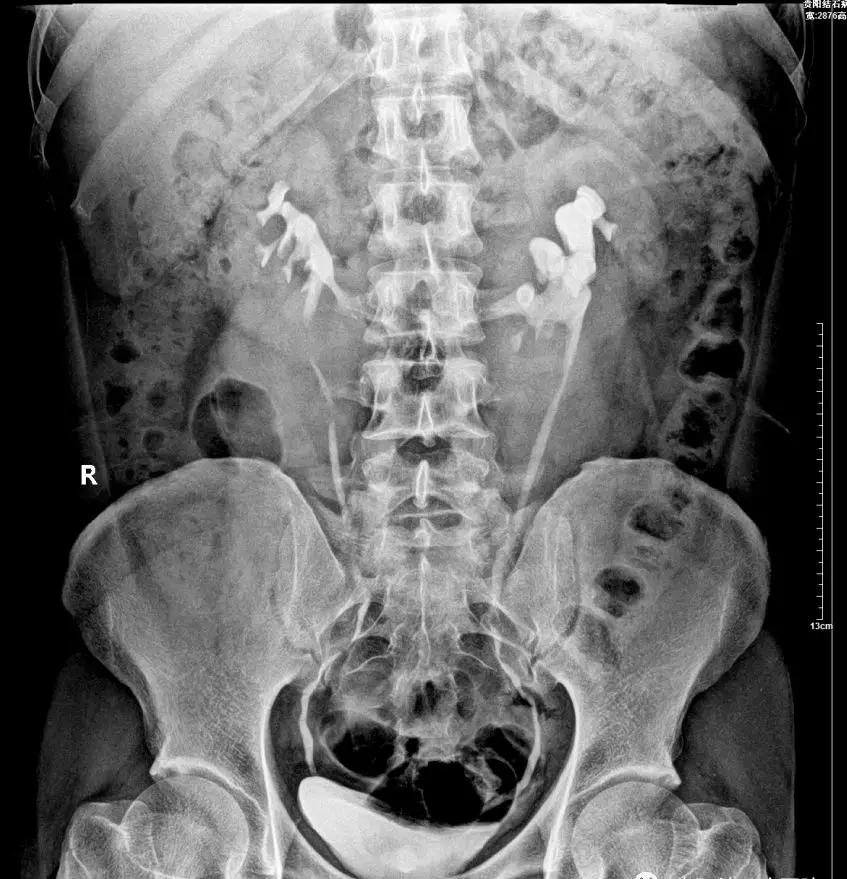

▲贵阳结石病医院为郭先生行静脉尿路造影 确认郭先生的双肾呈现明显的“马蹄肾”形态